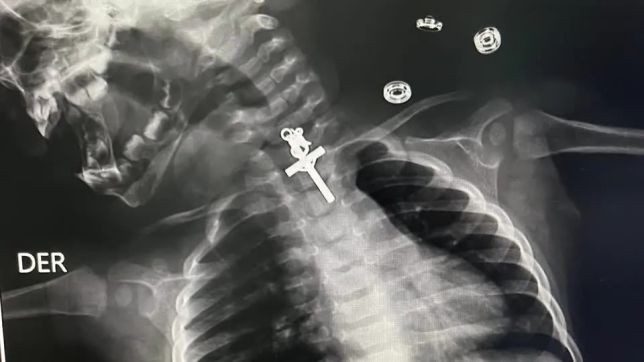

Imagens de raio-X mostraram um crucifixo alojado no esôfago de um bebê de 10 meses. A criança foi atendida no Hospital Victor Lazarte Echegaray, em La Libertad, no Peru, onde foi submetida a uma endoscopia para retirada do corpo estranho. O artefato foi removido com sucesso pela equipe médica no último sábado (11).

“O procedimento foi muito complicado porque era um crucifixo e estava alojado no terço superior do esôfago. Mesmo quando tentamos retirá-lo inicialmente, não conseguimos, estava preso, então tentamos várias vezes até que consegui retirar o corpo estranho”, disse o médico responsável, Luis Esteves Cabanillas.